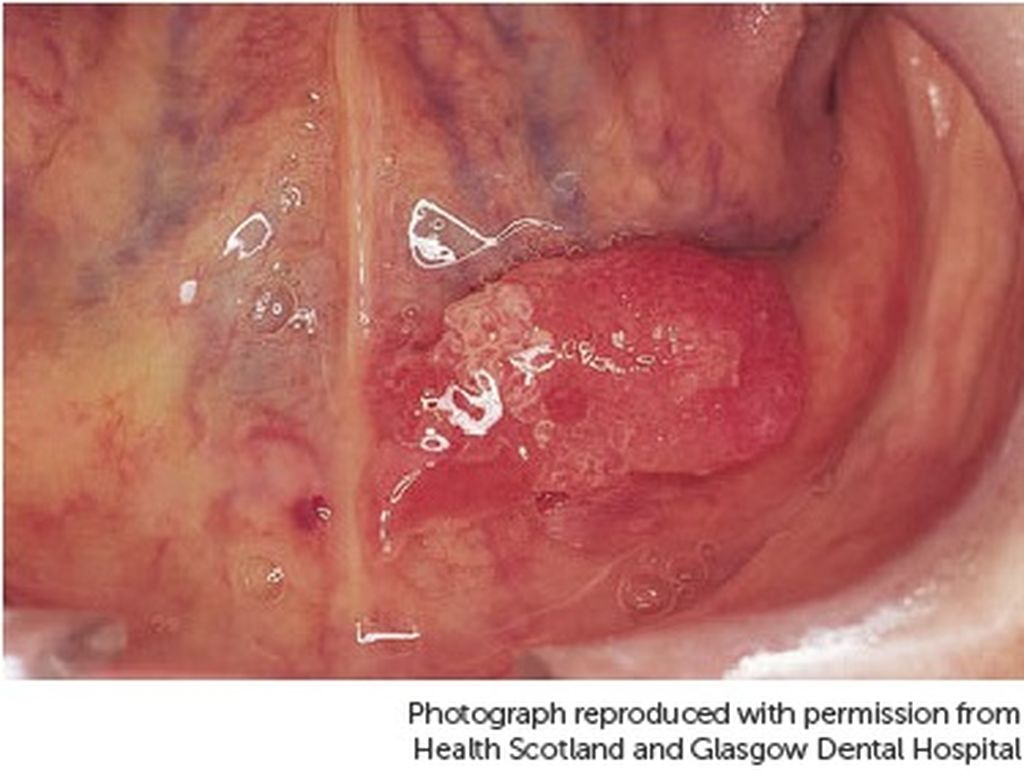

Ο καρκίνος της γλώσσας έχει πολλές μορφές, από τις οποίες η πιο κοινή είναι αυτή που ξεκινά από τα πλακώδη κύτταρα που βρίσκονται στην επιφάνεια της γλώσσας.

– Στον λαιμό: Δηλαδή στη βάση της γλώσσας, κοντά στον φάρυγγα, όπου παρουσιάζει και λιγότερα συμπτώματα. Αυτή η μορφή καρκίνου της γλώσσας διαγιγνώσκεται συνήθως σε πιο προχωρημένο στάδιο, όταν ο καρκινικός όγκος έχει μεγαλώσει σε μέγεθος και ενδεχομένως έχει εξαπλωθεί στα λεμφογάγγλια του λαιμού.

– κόκκινη η λευκή κηλίδα στην επιφάνεια της γλώσσας

– ανοιχτή πληγή (έλκος) στην επιφάνεια της γλώσσας

Στην παρακάτω gallery θα δείτε φωτογραφίες που αποτυπώνουν περιστατικά καρκίνου της γλώσσας.